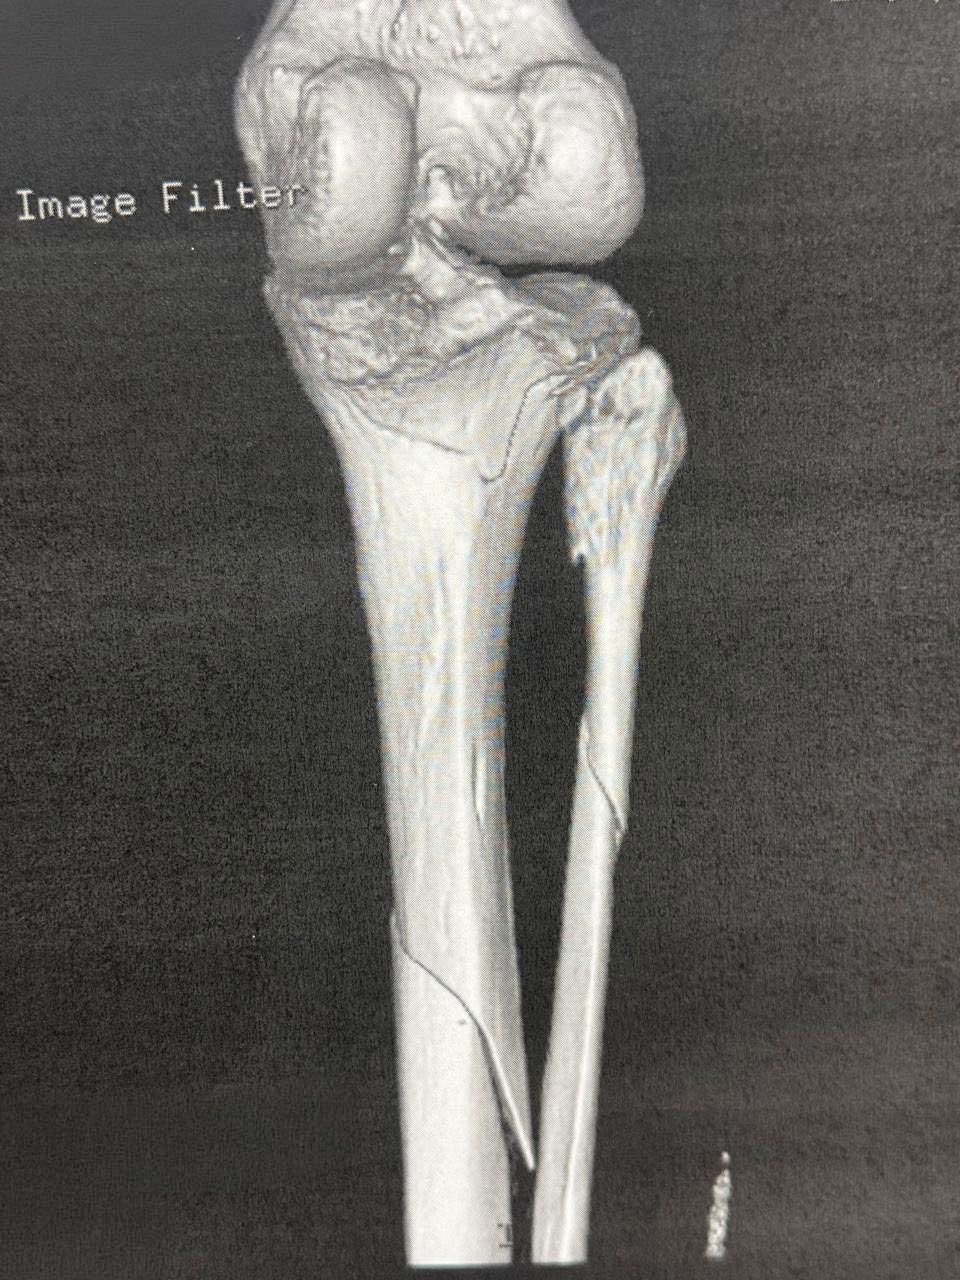

Σοβαρό ενδαρθρικό κάταγμα κνημιαίου πλατώ (Schatzker VI) — υψηλών απαιτήσεων αποκατάσταση με στόχο ανατομική ανάταξη και λειτουργικότητα γόνατος.

Αντιμετωπίσαμε ένα από τα πιο απαιτητικά και σύνθετα τραύματα στην ορθοπαιδική: σοβαρό ενδαρθρικό κάταγμα κνημιαίου πλατώ, Schatzker VI.

Το κάταγμα τύπου VI κατά Schatzker είναι το πιο βαρύ είδος κατάγματος του κνημιαίου plateau. Χαρακτηρίζεται από:

- Διπλοκονδύλιο κάταγμα (έσω + έξω plateau)

- Αποσύνδεση μεταφύσεως–διάφυσης (metaphyseal–diaphyseal dissociation)

- Συχνά συνοδό σοβαρή βλάβη μαλακών μορίων

Διάγνωση

Απεικόνιση

- Ακτινογραφίες (AP – lateral)

- CT scan (απαραίτητο για σχεδιασμό)

Schatzker type VI fracture is the most severe type of tibial plateau fracture.

It is characterized by:

- Bicondylar fracture (medial + lateral plateau)

- Metaphyseal–diaphyseal dissociation

- Often associated with severe soft-tissue injury